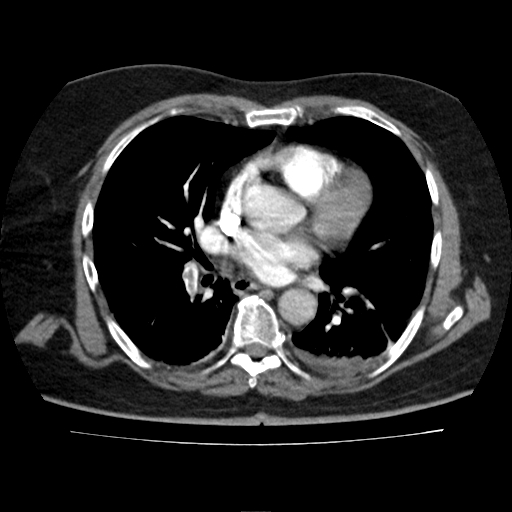

Angiotomografía de tórax con contraste intravenoso en fase angiográfica pulmonar.

Se identifican defectos de llenado intraluminal en arterias pulmonares segmentarias del lóbulo inferior derecho con extensión a ramas basales, así como defecto de llenado en arteria segmentaria basal posterior izquierda, compatibles con tromboembolia pulmonar periférica bilateral, de predominio derecho.

Se observan atelectasias basales posteriores bilaterales asociadas a derrame pleural laminar leve, mayor en el hemitórax izquierdo. Se documenta cardiomegalia leve y cambios ateroescleróticos vasculares. No se identifican masas pulmonares ni consolidaciones neumónicas extensas.

Tromboembolia pulmonar aguda periférica bilateral, con mayor afectación derecha, asociada a atelectasias pasivas y derrame pleural laminar.